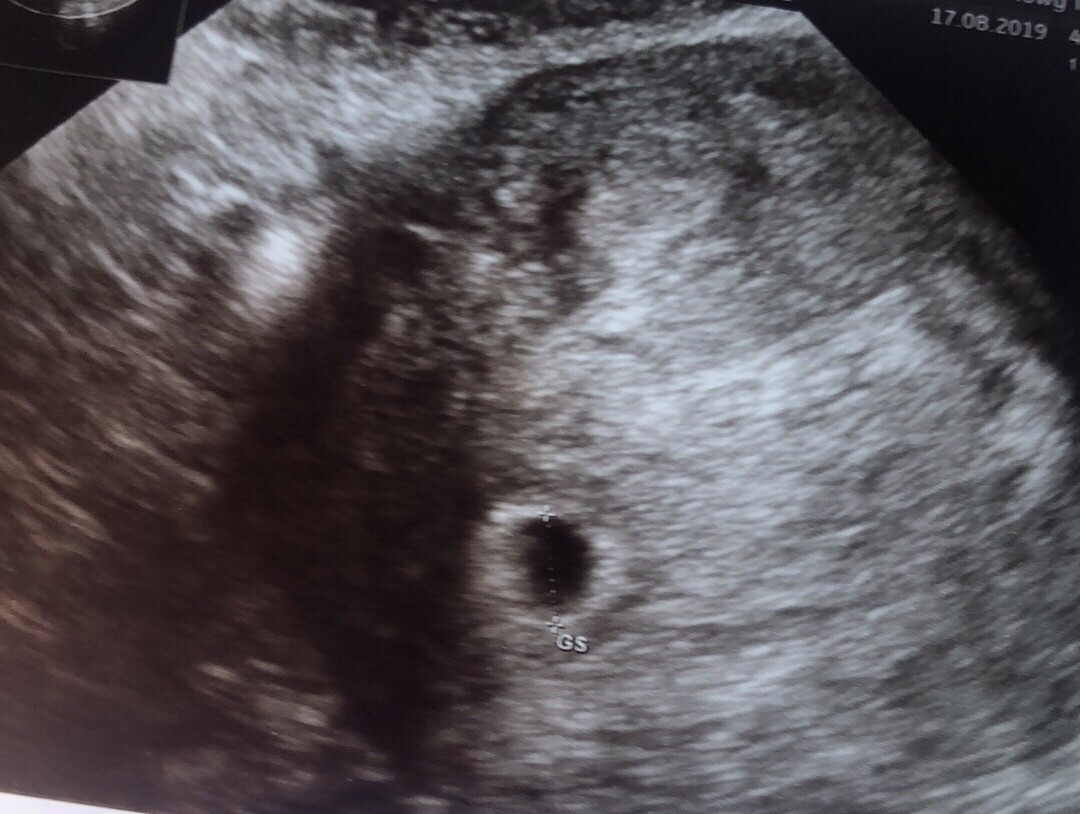

Zobacz załącznik 1011010

Wczoraj skierowanie do szpitala brak zarodka - podejrzenie ciąży pozamacicznej.

A dzisiaj piękny pęcherzyk! Ciąża po prostu młodsza.

ZOSTAJE z WAMI! Piękne uczucie :-)

Dziewczyny nigdy nie przestańcie walczyć!

Beta z dzisiaj 2000 :-) I pamiętajcie wcale nie musi być widać pęcherzyka przy becie 1000-1500 często jest to 2000-2500 :-)